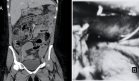

La ecografía abdominal inicial mostró dilatación de la vía biliar intra y extrahepática, con un colédoco de 8 mm de diámetro. La vesícula biliar presentaba paredes de grosor normal sin evidencia de litiasis.

Posteriormente, tras la corrección de la deshidratación, se realizó tomografía computarizada abdominal que reveló hallazgos compatibles con pancreatitis crónica avanzada, incluyendo calcificaciones parenquimatosas, dilatación irregular del conducto pancreático principal y pérdida de la arquitectura glandular normal.

Además, se identificó trombosis aguda de la vena esplénica con hematoma esplénico asociado. No se observaron lesiones ocupantes de espacio ni signos de abscesos pancreáticos.